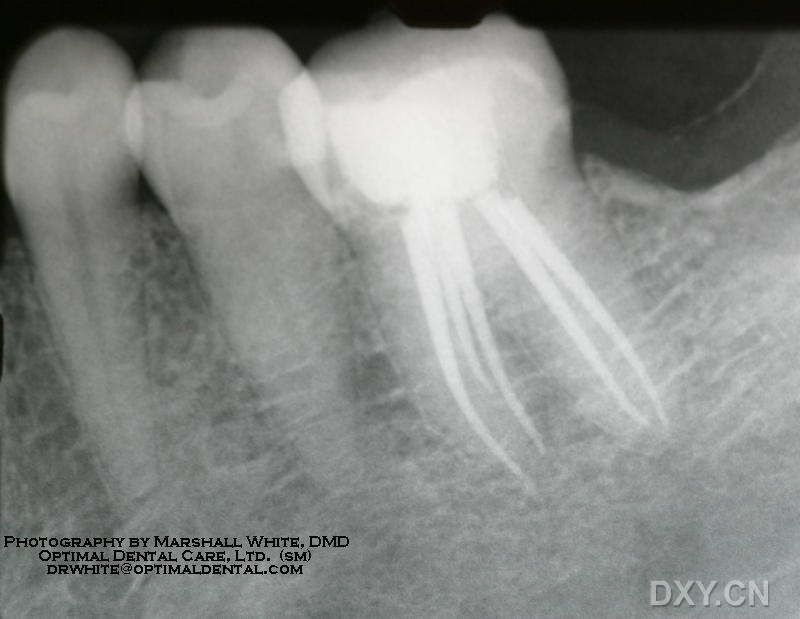

53岁患者李某,诊断为:牙冠隐裂,慢性牙髓炎,在第922医院口腔科就诊。入科后进行相关检查,排除绝对手术禁忌症,口腔科杨懿主任利用根管马达进行根管扩大、清理根管,在治疗过程中李某几乎无不适感,治疗过程标准化、安全舒适、治疗后功能恢复良好,三周后进行烤瓷牙冠修复,一周后李某特意来医院告知经过治疗后,吃饭与以前完全一样,没有其他任何不舒服的感觉。

根管马达的动力旋转与往复运动为临床医生使用牙锉扩大根管提供了动能,使根管预备更容易进行,医生们能够观察到根管口和牙髓底部,同时体验到不同的触觉反馈,大大提高了根管治疗的准确性和安全性。

适用于口腔内科牙髓炎、根尖周炎等根管治疗,是根管治疗术的重要补充和替代的治疗方法。

适应症:适用于口腔内科牙髓炎、根尖周炎等根管治疗。

禁忌症:有心脏病、精神类等疾病及张口困难者。

使用传统手工器械根管治疗,过程繁琐、费时费力、病人占用椅位时间长,多数医院已淘汰而采用了根管马达预备系统后,使预备流程标准化、高效化、减少医生劳动强度和病人在椅位时间,能极大地提高治疗效果及医生工作效率,同时还可以消除根管扩大器械因脱落后造成咽喉、食道、气道异物。